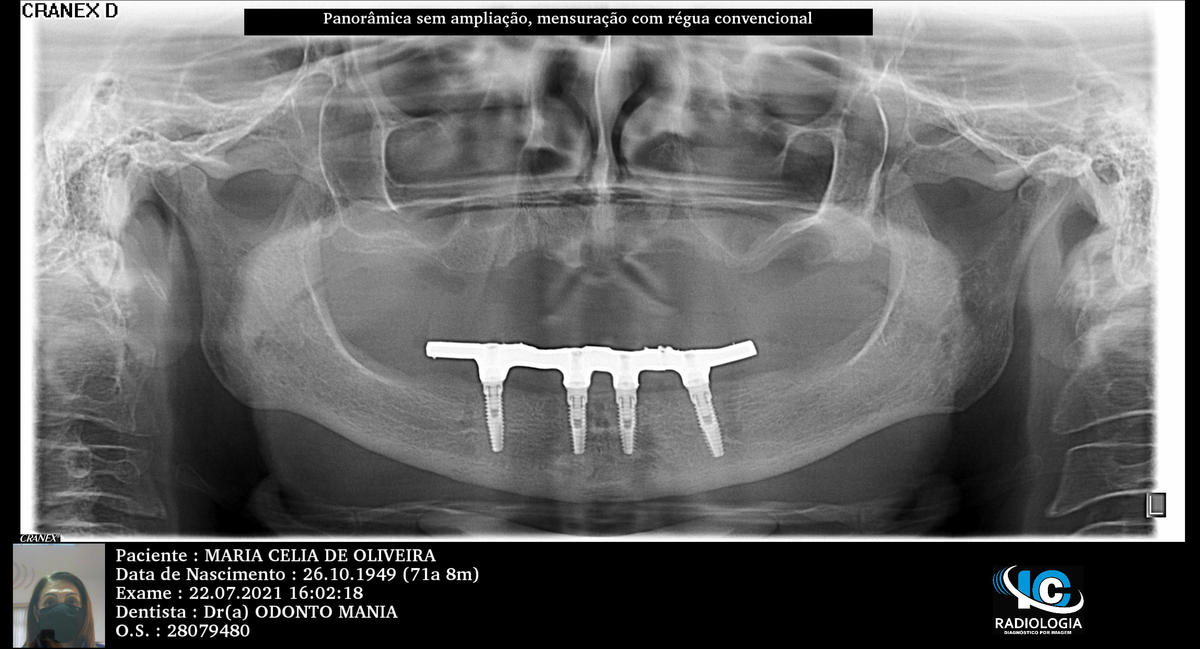

PRÓTESE TOTAL FIXA EM IMPLANTES

M.C.O.